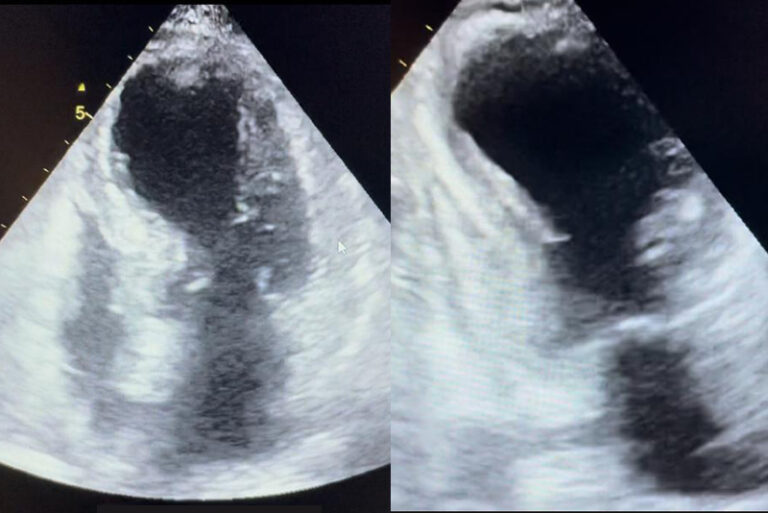

近日有一位日籍中年男性遊客在澳門觀光塔跳笨豬跳後死亡,據報導,死者跳完笨豬跳後身體表面並無明顯傷痕,但其後出現氣促、呼吸及心跳停頓,送院搶救後不治。刺激的極限運動/活動或劇烈的情緒波動,會引發腎上腺素等壓力荷爾蒙急劇上升,對心血管系統造成壓力,有機會引起急性心臟病發,如急性心肌梗塞、心室顫動、主動脈剝離(內膜撕裂)等。本文會討論一種身體應對壓力時誘發的急性心肌病 - 章魚壺心肌病變 (Takotsubo Cardiomyopathy )。